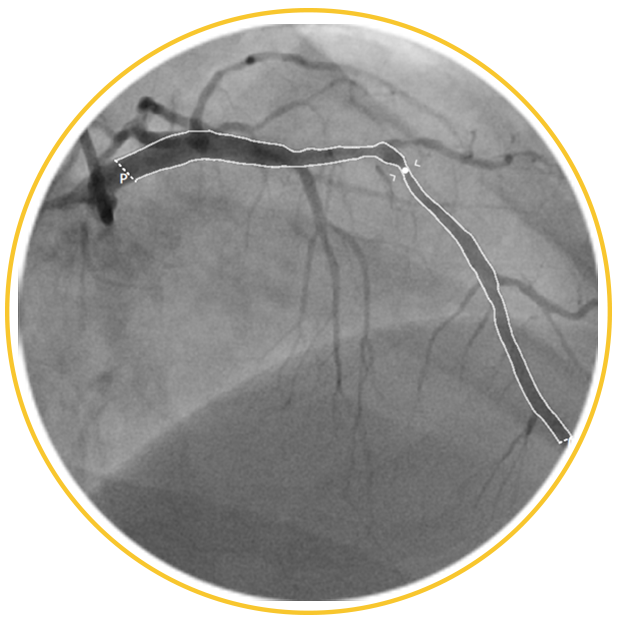

Powered by a Single Angiogram

Advanced flow + geometry analysis provides accurate FFR of a target vessel from only one angiogram, not two or three

Automated Segmentation

Reduce manual tracing with AI-powered vessel segmentation